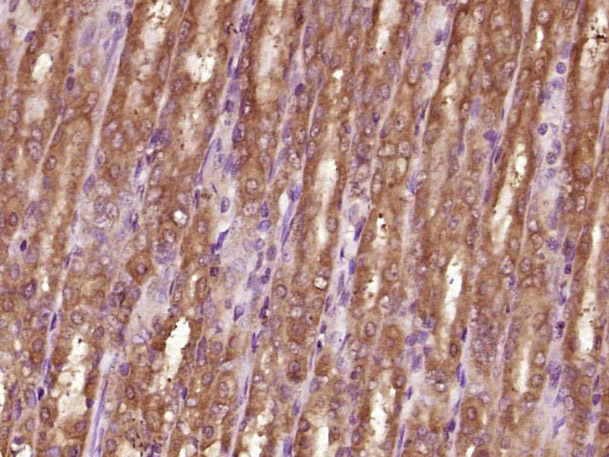

Antigen retrieval: citrate buffer ( 0.01M, pH 6.0 ), Boiling bathing for 15min; Block endogenous peroxidase by 3% Hydrogen peroxide for 30min; Blocking buffer (normal goat serum,C-0005) at 37℃ for 20 min;

Incubation: Anti-Vinculin Polyclonal Antibody, Unconjugated(bs-6640R) 1:200, overnight at 4°C, followed by conjugation to the secondary antibody(SP-0023) and DAB(C-0010) staining